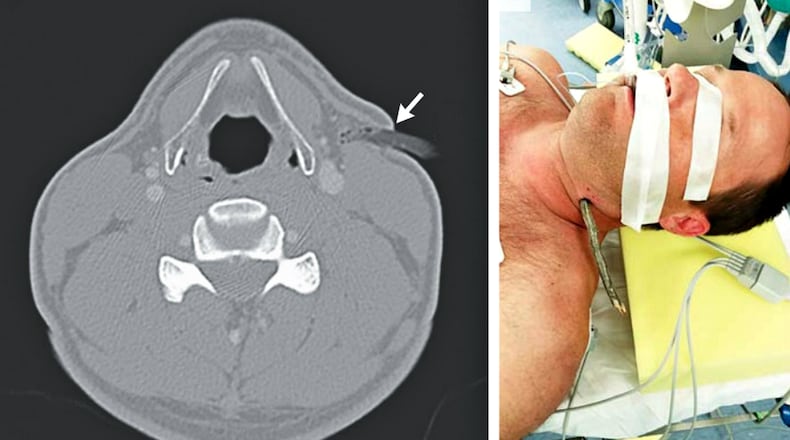

Sticking out of the let side of his neck was a small tree limb.

A CT scan at the University of New Mexico facility showed the small branch penetrated just over a half-inch into the man’s neck, narrowly missing key nerves and arteries.

The rider was taken to surgery where the limb was removed without complications, and the patient was released with no complications.